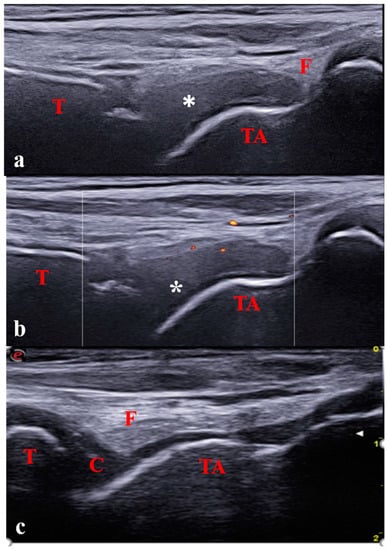

- Jousse-Joulin, S.; Breton, S.; Cangemi, C.; Fenoll, B.; Bressolette, L.; de Parscau, L.; Saraux, A.; Devauchelle-Pensec, V. Ultrasonography for Detecting Enthesitis in Juvenile Idiopathic Arthritis. Arthritis Care Res. 2011, 63, 849–855. [Google Scholar] [CrossRef]